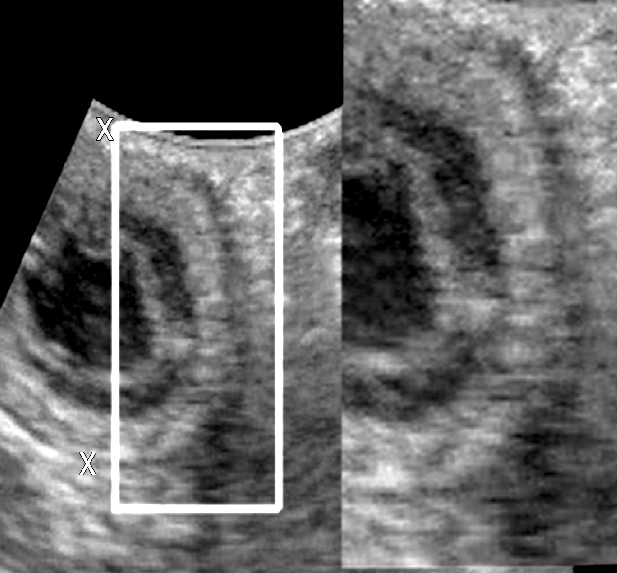

사진처럼 개의 복부 초음파 검사에서 위십이지장 연접부, 소위 PDJ에 해당하는 부분에 에코가 높게 관찰되는 경우는 흔하게 관찰되어 실제 임상적인 의미를 두지 않는데 이에 대한 명확한 문헌적 근거가 나와 소개한다.

위 십이장의 해부학적 분기점으로 섬유결합조직이 많아 보이는 현상으로 이해하면 무리가 없을것이다.

임상에서 의미가 없으니 어느날 갑자기 눈에 띄었다고 너무 놀래지 말아야 할것이다.